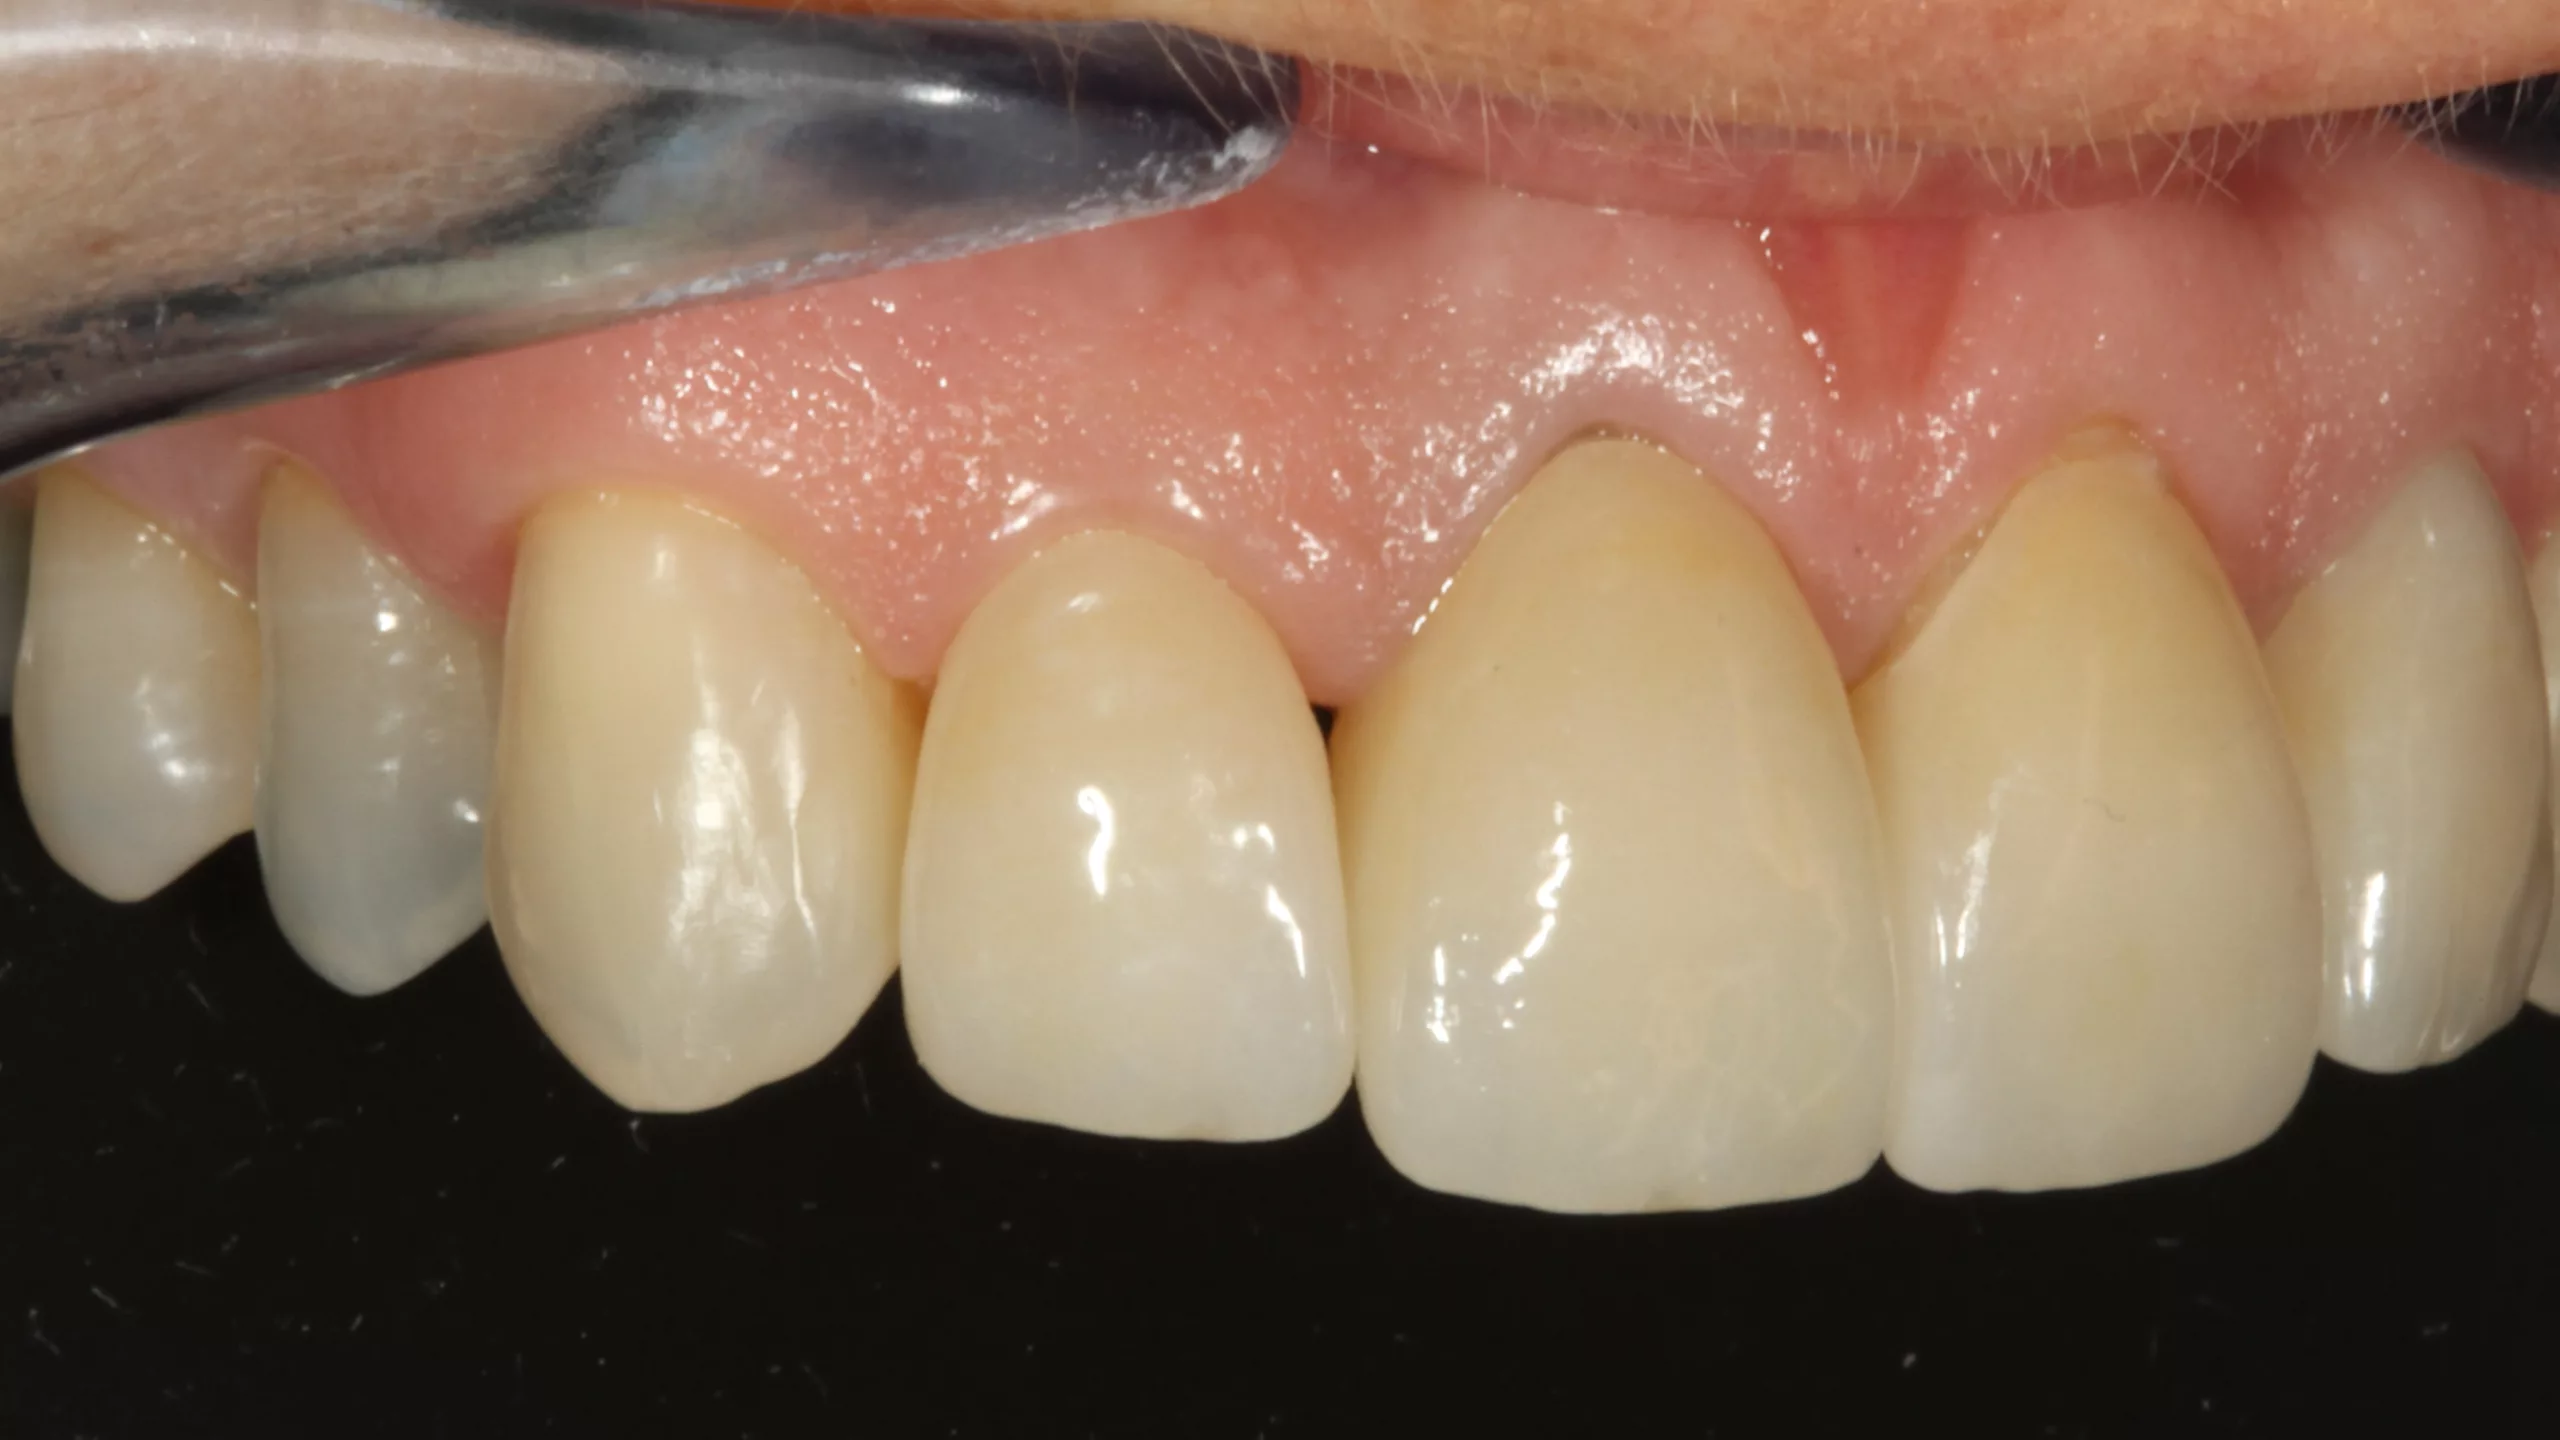

Die Abbildung 19 zeigt den bereits mit Kofferdam isolierten Zahn 22 nach der Reinigung der Oberfläche, die Abbildung 20 die Phosphorsäurekonditionierung der gesamten Klebefläche (Schmelz- und Dentinareale ließen sich nur schwer voneinander optisch differenzieren). Da der Visalys Tooth Primer auf mit phosphorsäuregeätztem Dentin genauso effizient funktioniert wie in seiner originären, selbstkonditionierenden Primerfunktion, sollte im Zweifelsfall besser großräumiger mit dem Phosphorsäuregel geätzt werden. Die Abbildung 21 zeigt den konditionierten Zahnstumpf aus inzisaler Sicht, die Abbildung 22 von labial. Wie in allen vorangegangenen Fällen erfolgte im nächsten Schritt die Applikation des Visalys Tooth Primers, dessen Einwirken für 20 Sek. (Abb. 23 und 24) und das Verblasen der Überstände bzw. die sorgfältige Evaporation des Lösungsmittels mit dem Luftbläser. Mit diesem Schritt war die Vorbehandlung des Zahnes abgeschlossen. Auch diese Krone wurde mit Visalys CemCore in der Farbe Universal (A2/A3) adhäsiv befestigt. Die vollständige Überschussentfernung erfolgte erneut mit einem sauberen Bondingpinsel (kein Microbrush) noch vor der Polymerisation (Abb. 25). Die Abbildung 26 zeigt die versäuberte, eingeklebte verblendete Vollzirkonkrone noch unter Kofferdam, die Abbildungen 27 und 28 das finale klinische Gesamtergebnis der sehr zufriedenen Patientin.